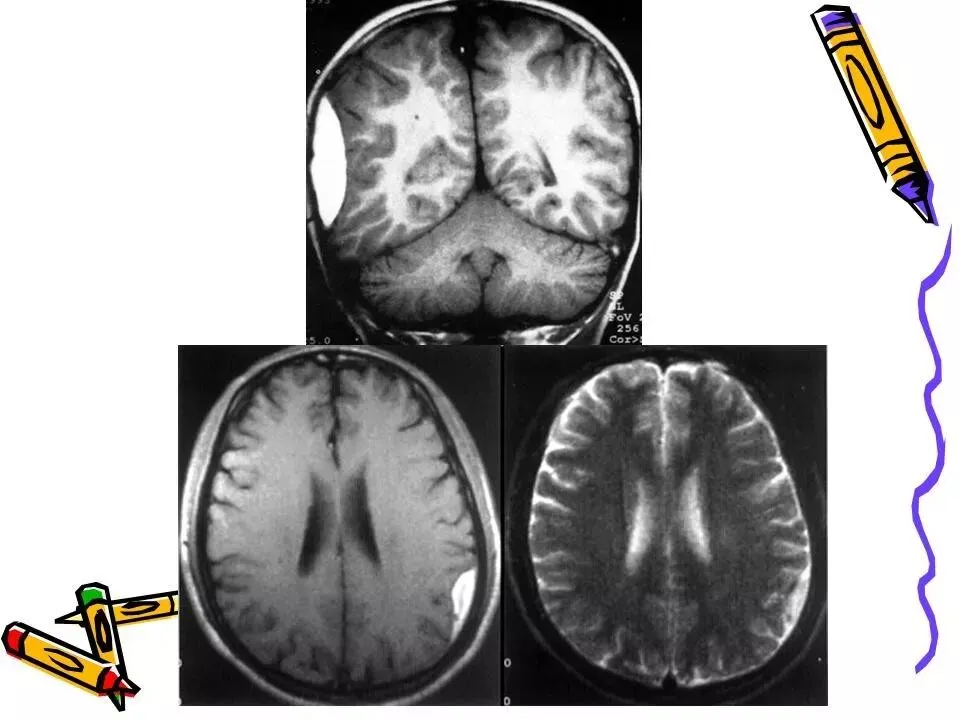

>常见颅脑外伤CT诊断(PPT)

常见颅脑外伤CT诊断(PPT)